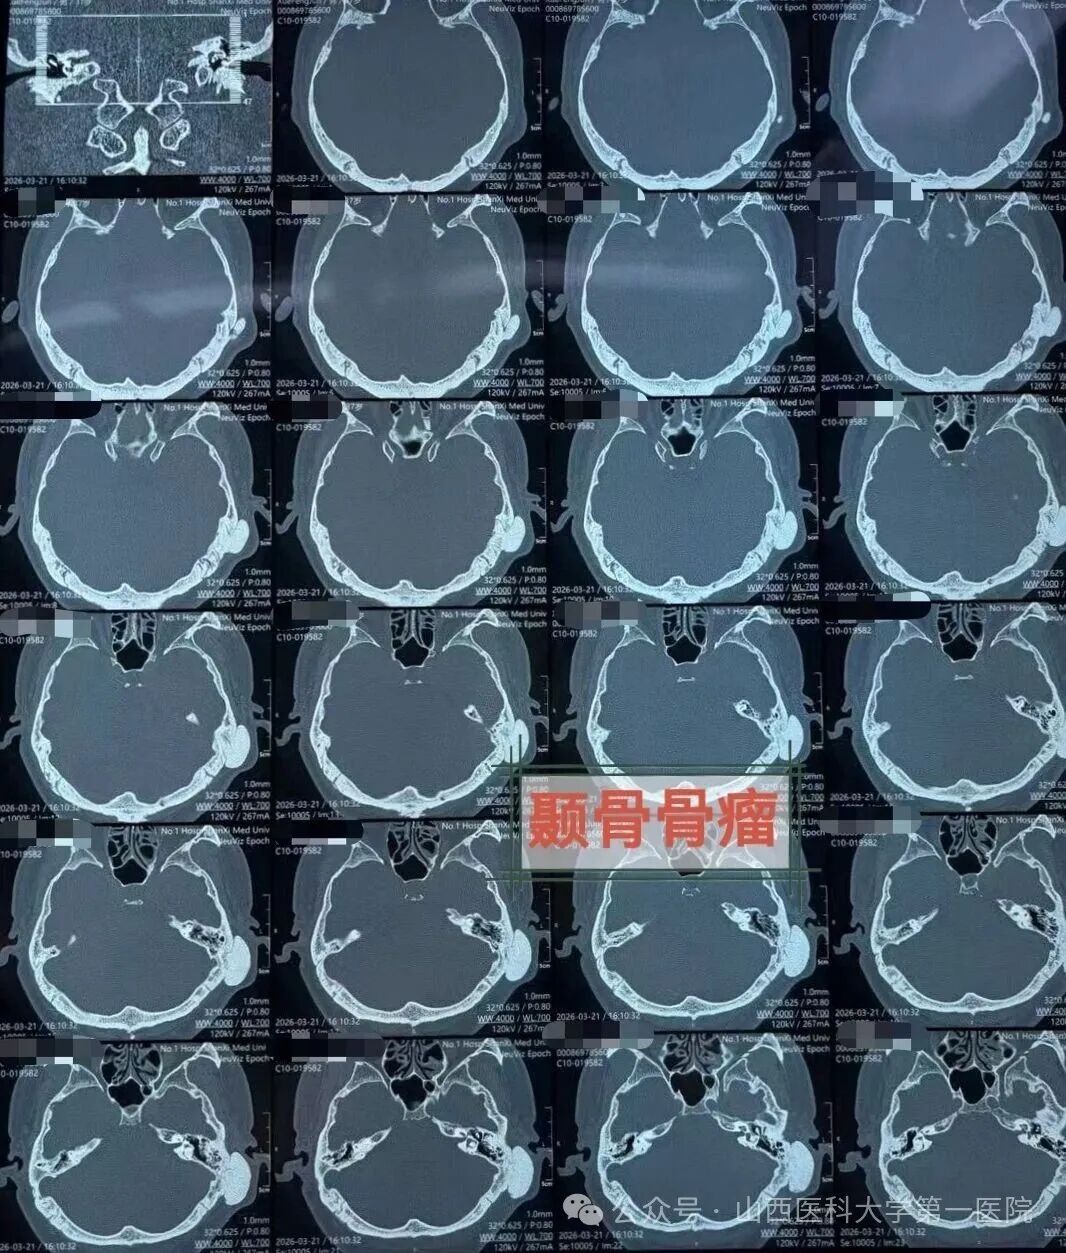

患者来自山西晋北,长期受间断性一侧偏头痛及头闷困扰,辗转求医无果,最终来到山医大一院耳鼻咽喉-头颈外科,经颞骨CT及头颅MRI检查,发现左侧颞骨鳞部有一约3.2cm×3.5cm×1.6cm的骨性肿瘤。肿瘤侵犯并破坏了颞骨鳞部、鼓部及乳突,波及颅中窝底,但未突入颅内,与静脉窦等重要神经血管关系密切。

经多学科会诊(MDT)讨论,决定采用经耳后鳞部-乳突进路手术。麻醉科医生实施插管全麻并全程监护,手术室护士密切配合,张海利主任医师与郁文捷副主任医师在显微镜下精准切除乳突及鳞部肿瘤,完好保护了重要血管及神经结构,彻底切除病变。